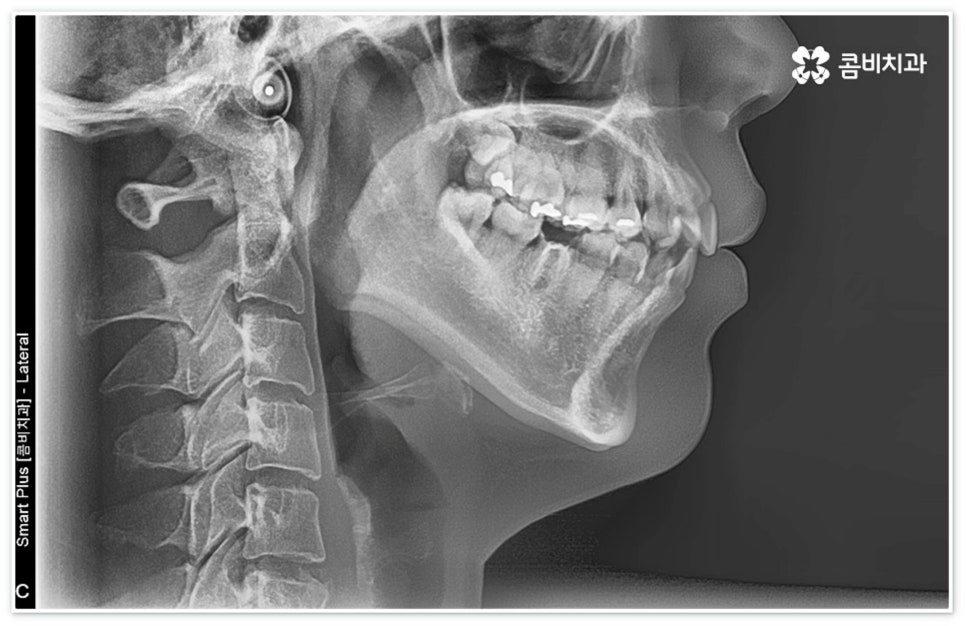

신경치료는 일견 간단해 보일 수 있으나 사람의 신경이 매우 얇고 또한 환자분들마다 신경관의 개수와 모양이 다 다르기 때문에 오염된 부위를 끝까지 깨끗하게 제거하기 위해서는 매우 섬세하고 뛰어난 기술력을 요하므로 다양한 임상 경험을 통해 풍부한 노하우를 가지고 있는 의료진과 함께 하실 필요가 있습니다.

이때 환자분들마다 상황이 다를 수 있는데 예를 들어 교정 치료 중 충치 치료 (신경 치료) 및 발치와 임플란트 식립과 같은 고난도의 치료들을 함께 진행해야 하는 복잡한 케이스의 경우에는 더욱 시술자의 숙련도가 중요하다고 할 수 있어요. 의료진의 자격증, 경력 사항, 분과별 협진 여부 등을 잘 알아 보시고 필요한 치료들을 모두 통합적으로 진행할 수 있는지, 또한 환자분들의 상황을 꼼꼼하게 살필 수 있는 3D CT 와 같은 정밀 검진 기계를 갖추고 있는지 등을 체크해 보신 후에 처음부터 끝까지 책임 진료하는 의료진과 철저한 케어 시스템을 갖추고 있는 치과를 선택하셔서 제 때 필요한 치료를 받으시길 권유드리고 있습니다.